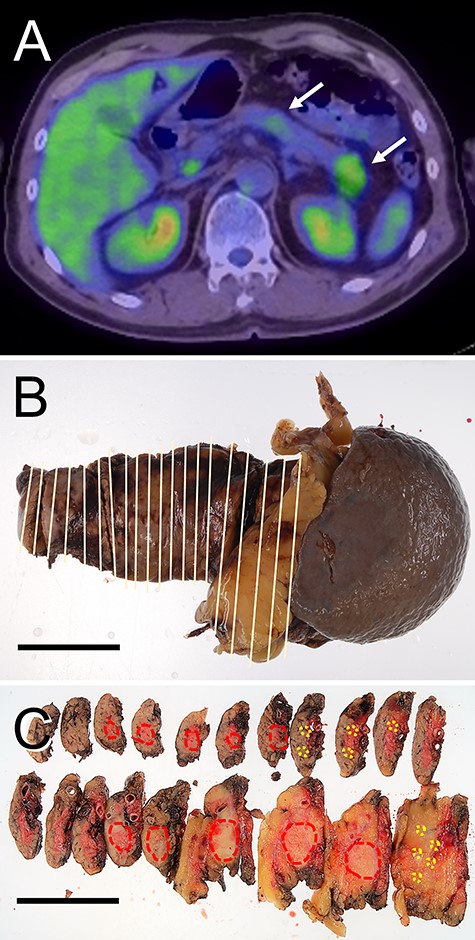

Radiological features and macroscopic findings of Case 2. (A) FDG-PET: two nodular masses with high SUV were detected in the pancreas (white arrows). (B) Macroscopic finding of the resected pancreas. (C) Two nodular lesions (red circles) and foci of small lesions (yellow circles) were indicated on the cut surface.

A nodular mass was noted in the body or tail of the pancreas by USG in three cases (Figs 1–3). Endoscopic ultrasound-guided fine needle aspiration gave negative result in all patients. No lesion was detected by computed tomography (CT) (Fig. 1B and Table 1). Low-intensity mass was detected in the body or tail with T1-weighted imaging of magnetic resonance imaging (MRI: Fig. 1C and Table 1). 18F-fluorodeoxyglucose positron-emission tomography (FDG-PET) detected two lesions with high standardized uptake value (SUV) in the body and tail in Cases 1 and 2 (Figs 1D and2A and Table 1) and one lesion in the body in Case 3 (Fig. 3A and Table 1). In the resected pancreas, two lesions were found in the body and tail of the pancreas in Cases 1 and 2 (Figs 1F and2C, red circles) and one lesion of the pancreatic body in Case 3 (Fig. 3C, red circles). Small foci of lymphoid hyperplasia were noted in all cases (Figs 1F, 2C and3C, yellow circles).